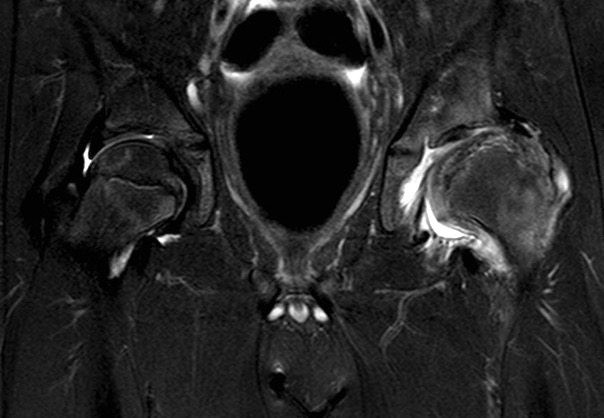

MRI

Advantage

- can assess amount of cartilaginous head outside of acetabulum

- very good way of assessing containment of cartilage head